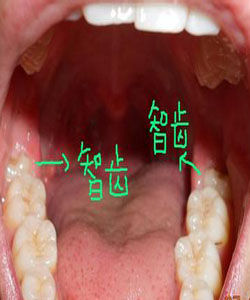

生長方向

智齒生長的位置特殊,給它的清潔和治療帶來許多問題,常引起的疾病有齲齒(俗稱蛀牙)、牙周炎、牙髓炎:由於智齒在最裡面,日常刷牙不容易清潔,容易產生蛀牙,且智齒往往由於萌發空間不足出現脹痛,還會侵犯鄰牙,造成牙疼。由於沒有對咬牙,有時智齒會過度萌發伸長,進而影響咬合;還有時會萌發不足成為阻生齒,引起牙列不齊,冠周間隙感染,張口困難。智齒是第三大臼齒,對相鄰的第二磨牙有重要影響。由於大多數智齒是前傾阻生的,約呈45度角頂在第二磨牙上,從而形成一個牙冠夾角,容易嵌塞食物,久之導致第二磨牙齲壞,甚至牙髓炎,就算沒有那么嚴重也會影響第二磨牙的壽命。拔除適應症

智牙 2.造成鄰牙病變:通常患者不自知,而由牙醫以X光診斷得知。通常智齒萌發的空間不足,而會倒在第二大臼齒上,因而造成第二大臼齒清潔不易,甚至是牙齒部分吸收的現象,造成患者不舒適或牙疼。